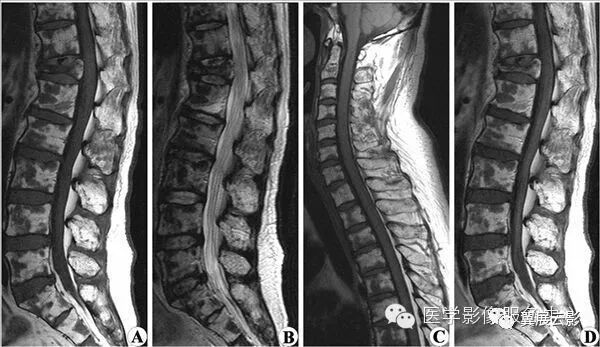

【MRI图片】:

【影像表现】:MRI平扫T1WI(A)、T2WI(B)示 腰1椎体呈楔形改变(↑),胸12~腰1椎间盘后突。【影像诊断】:椎体压缩性骨折。